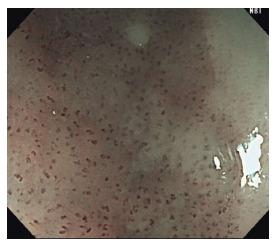

Esophageal cancer is one of the leading causes of cancer-related death and is associated with high morbidity and mortality. It carries a poor prognosis as more than half of patients present with advanced and unresectable disease. One contributing factor is the increased risk of lymph node metastases at early stages of disease. As such, it is essential to detect squamous cell neoplasia (SCN) at an early stage. In order to risk stratify lesions, endoscopists must be able to perform image enhanced endoscopy including magnification and Lugol's chromoendoscopy. The assessment of both the horizontal extent and depth of any lesion is also of utmost importance prior to treatment. Endoscopic mucosal resection and submucosal dissection remain the standard of care with literature supportive their respective use. Radiofrequency ablation and other endoscopic treatments are currently available although should not be considered first line at this time. Our objective is to review the current options for the endoscopic diagnosis and treatment of esophageal SCN.

食管癌是癌症相关死亡的主要原因之一,其发病率和死亡率都很高。由于超过一半的患者就诊时已处于晚期且无法切除,其预后较差。一个促成因素是疾病早期淋巴结转移风险增加。因此,早期检测鳞状上皮瘤变(SCN)至关重要。为了对病变进行风险分层,内镜医师必须能够进行包括放大内镜和卢戈氏染色内镜检查在内的图像增强内镜检查。在治疗前,评估任何病变的水平范围和深度也至关重要。内镜黏膜切除术和黏膜下剥离术仍然是标准的治疗方法,有文献支持各自的应用。目前虽然有射频消融和其他内镜治疗方法,但目前不应将其视为一线治疗方法。我们的目的是综述目前食管SCN的内镜诊断和治疗选择。